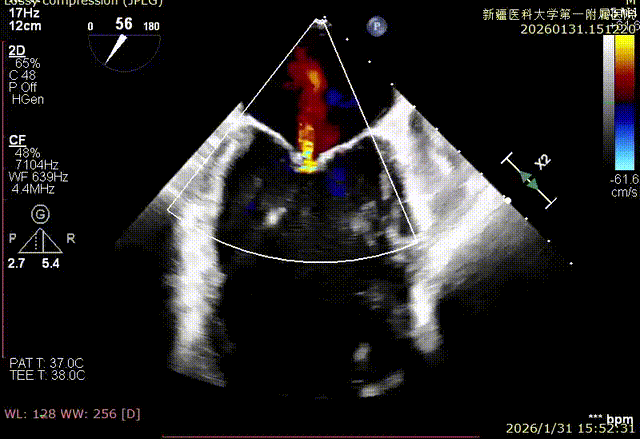

XPLAN切面中重度反流

Bicom切面中重度反流